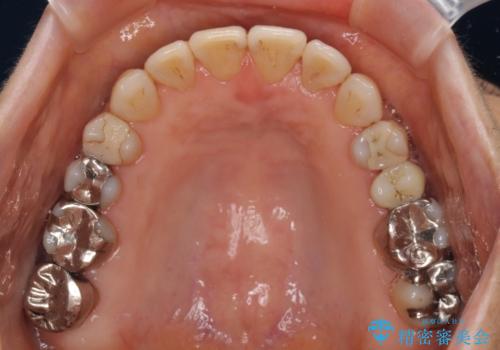

- 前歯の上下スペースと前歯の隙間を気にして来院された患者様です。

インビザラインにより上下の前歯の隙間を閉じながら、IPRを用いて口元の突出感を合わせて改善していくこととしました。

上下の隙間に舌が入り込むことが、すきっ歯やオープンバイトの原因であったため、舌の筋肉のトレーニングも並行して行い、後戻りの抑制を図りました。